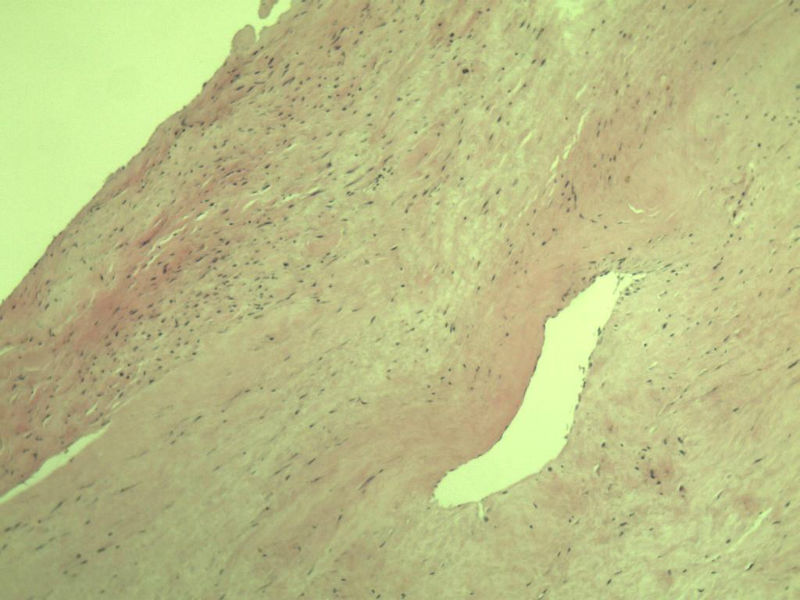

男,51岁, 4月前患者无意中发现右腘窝一包块,约核仁大小无疼痛, 4月来包块进行性生长

灰褐类圆形包块一个,直径 5 cm,切面灰白,实性,编织状。 请各位老师看看 是什么? 谢谢!